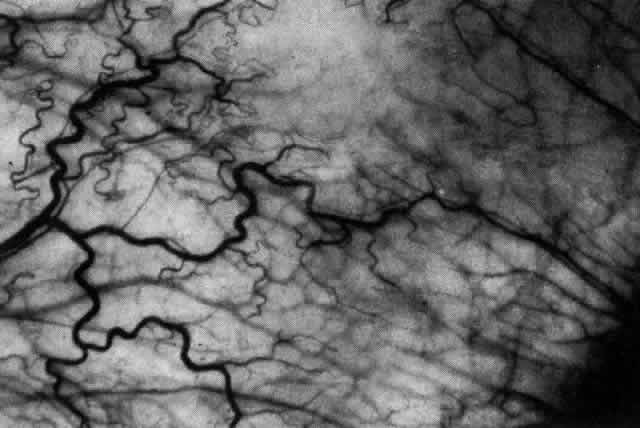

The redness of simple episcleritis may be intense, varying from a fiery-red or a brick-red discoloration to a mild red flush, but it does not have the bluish tinge that is seen in scleritis. The distribution is usually sectorial but can involve the whole anterior segment of the globe. The episcleral vessels are engorged but retain their normal radial position and architecture (Figs. 13 and 14; Color Plate 1A). In simple episcleritis, there is a diffuse edema of the episcleral tissues. These tissues are sometimes infiltrated with gray deposits that appear yellow in red-free light. Surprisingly, the eye is rarely tender to the touch.

Fig. 14. Diffuse inflammation. Superficial vessels are maximally engorged and retain their radial pattern and architecture. (See Figures 27 and 34.) (Watson PG: Connective tissue disorders and the eye. In: Recent Advances in Ophthalmology, Vol 5, pp 214–277. London, Churchill-Livingstone, 1975)